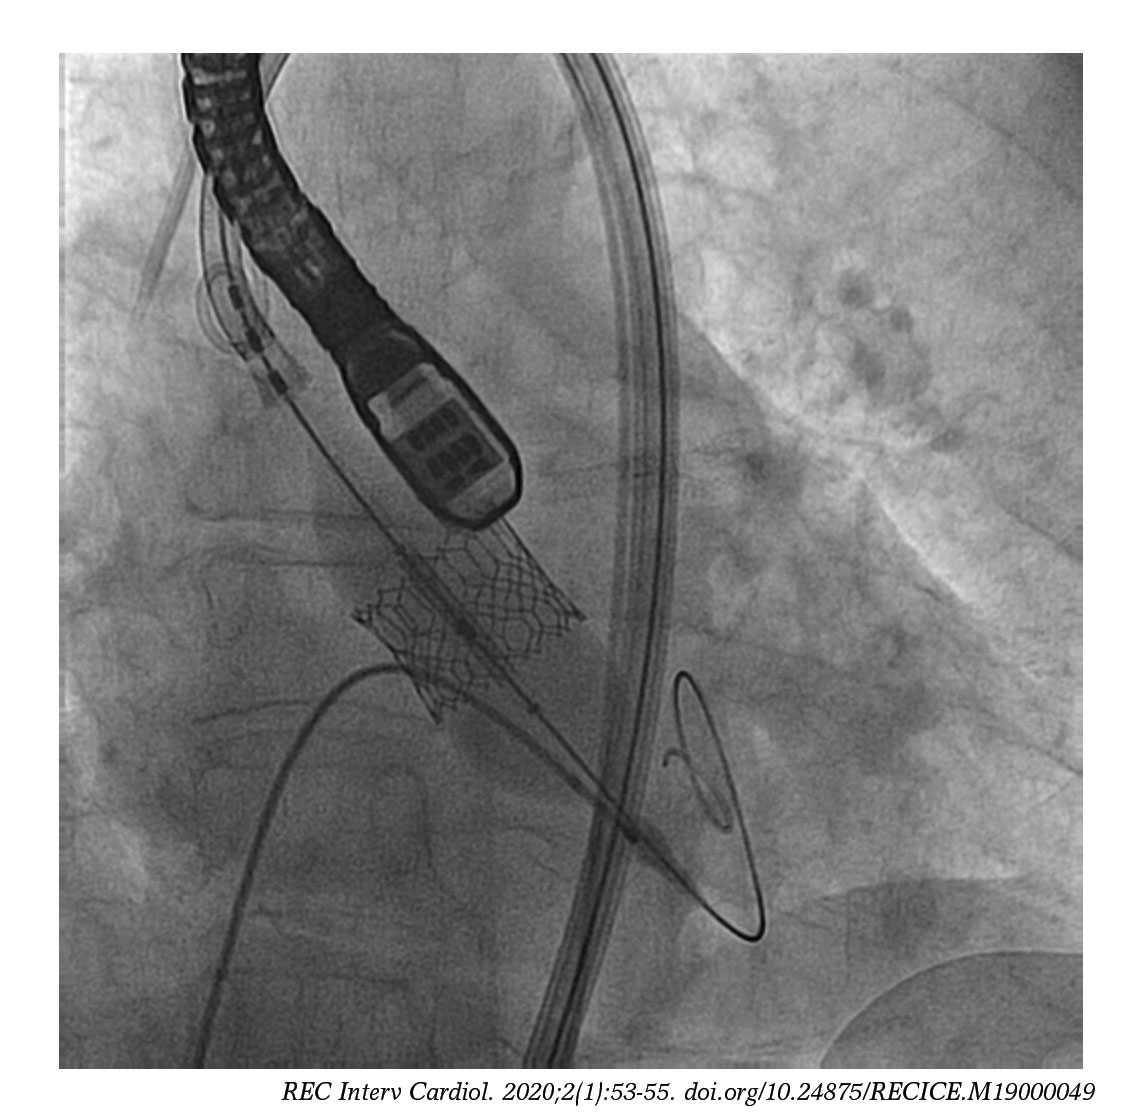

From recintervcardiol.org

Simultaneous transfemoral TAVI and angioplasty of unprotected Microclip Heart The mitraclip® is a minimally invasive procedure used to treat patients with mitral valve regurgitation. Learn about this mitral regurgitation treatment option. A specially designed device is. Mitraclip is a simple procedure to fix your leaky heart valve. A clip used to repair damaged heart valves sharply reduced deaths among patients with a grim prognosis. The mitraclip procedure is performed. Microclip Heart.